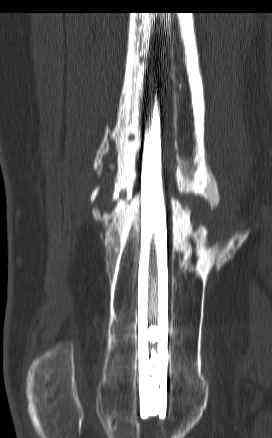

16 yr old boy, high energy motorcycle trauma trauma in July 2005 with:

- distal femoral fracture L

july 05: LISS femur, LCP plate tibia, double recon. plate post. acetabulum

feb 07: retrograde nail + bone graft + BMP

may 07: dynamisation nail

sept 07: locking screw removal (max. dynamisation reached)

nov 07: persistant non-union distal femur; other fractures healed